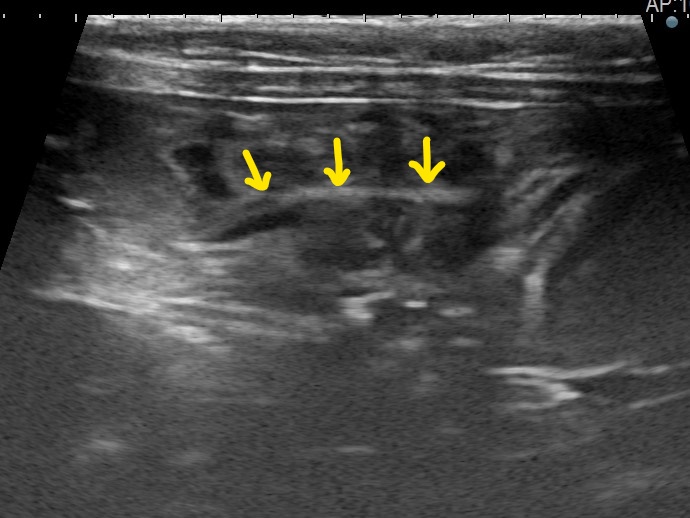

矢印:腸管内のひも状異物